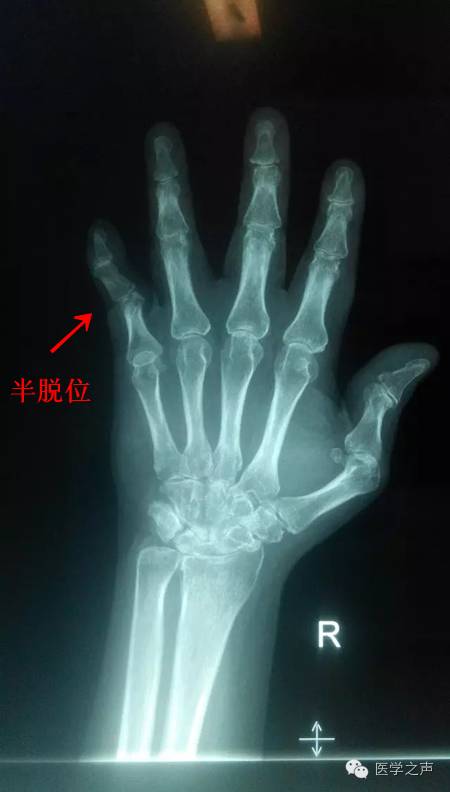

双手指间关节周围软组织稍肿胀,关节面模糊,关节间隙变窄,关节邻近骨质疏松,其间可见斑点状及小囊状骨质密度减低区,左手第1掌指关节及右手第5指关节呈半脱位,各腕骨骨质疏松,边缘不清,见斑点状及小囊状骨质密度减低区。

1.双手类风湿性关节炎。

2.左手第1掌指关节及右手第5指关节呈半脱位。